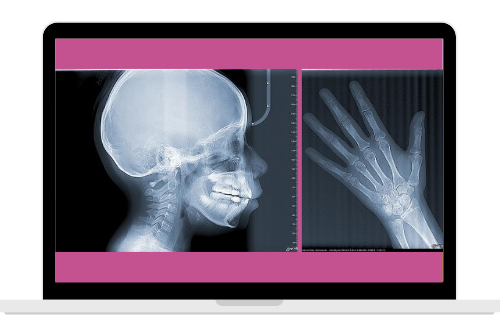

$279.00 MXN Impresa en película radiográfica +Digital

(precio de lista

$357.24 MXN)Alta Definición

Entrega digital a tu WhatsApp y/o e-mail

Lateral de cráneo, Antero – Posterior, Waters, Carpal, Towne

Proyección del sub – mentón vertex del cráneo (longitud de 20cm)

Con tan solo un escaneo de 10 segundos